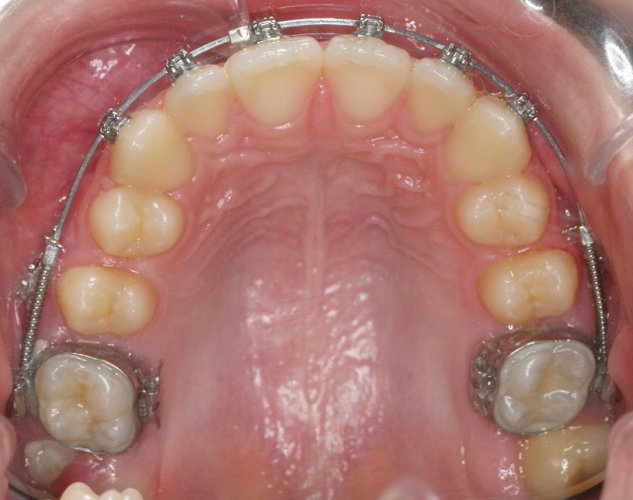

FEBRERO 2013 - Upper Occlusal

Image 4 De 4